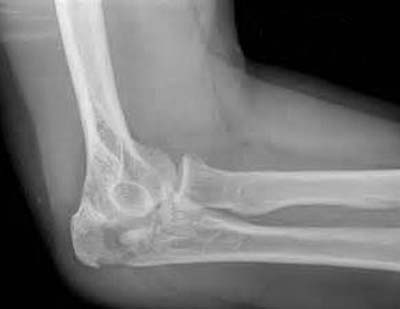

Инструментальные методы исследования, применяемые в диагностике внутрисуставного перелома, следующие:

- рентгенологическое обследование – в силу того что рентгенологическое оборудование имеется даже в небольших клиниках, метод остается наиболее популярным методом диагностики внутрисуставных переломов. С помощью рентгенологического снимка выявляют перелом, уточняют плоскость повреждения кости, положение костных фрагментов, наличие свободных отломков излома. Снимок делают в нескольких проекциях. При необходимости исследование проводят в специальных укладках и тангенциальных (косых) проекциях;